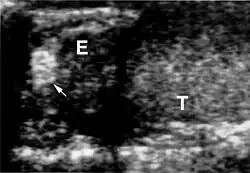

Die Diagnose VHL-Syndrom wird beim Vorhandensein von kapillären Hämangioblastomen (gefäßreichen Tumoren) im ZNS oder der Netzhaut des Auges gestellt. Weitere zum VHL-Komplex gehörende Tumoren (Phäochromozytom, Nierenzellkarzinom) oder eine entsprechende Familienanamnese treten hinzu. In der Kernspintomografie stellen sich die Hämangioblastome als kontrastmittelaufnehmende Knötchen dar.

Das klinische Spektrum der Erkrankung umfasst neben den Affektionen von Augen und Kleinhirn das Auftreten von Hämangioblastomen im Bereich des Hirnstamms und des Rückenmarkes. Sodann werden Nierenzellkarzinome (Erkrankungsrisiko liegt bei 25 – 45 %, meist ab dem 50. Lebensjahr), Pankreaszysten, Phäochromozytome, Nebenhodenzysten und eine Polyzythämie beobachtet.

Die Patienten entwickeln gutartige geschwulstähnliche Gewebsveränderungen (Angiome) vornehmlich im Bereich der Netzhaut des Auges und des Kleinhirns. Letzteres wurde auch als Lindau-Tumor oder Lindau-Syndrom bezeichnet. Im zentralen Nervensystem können darüber hinaus auch der Hirnstamm und das Rückenmark, selten das Großhirn betroffen sein. Charakteristisch für das VHL-Syndrom ist, dass sich aus Vorformen des Bindegewebes Geschwülste entwickeln, die aus Gefäßknäueln bestehen. Viele Patienten haben auch Gewebsveränderungen im Bereich von Niere (Nierenzellkarzinome), Nebenniere (Phäochromozytom) und Bauchspeicheldrüse. Bei Männern kann der Nebenhoden betroffen sein. Diese Gewebsveränderungen können harmlos sein, sich aber auch zu bösartigen Tumoren entwickeln.